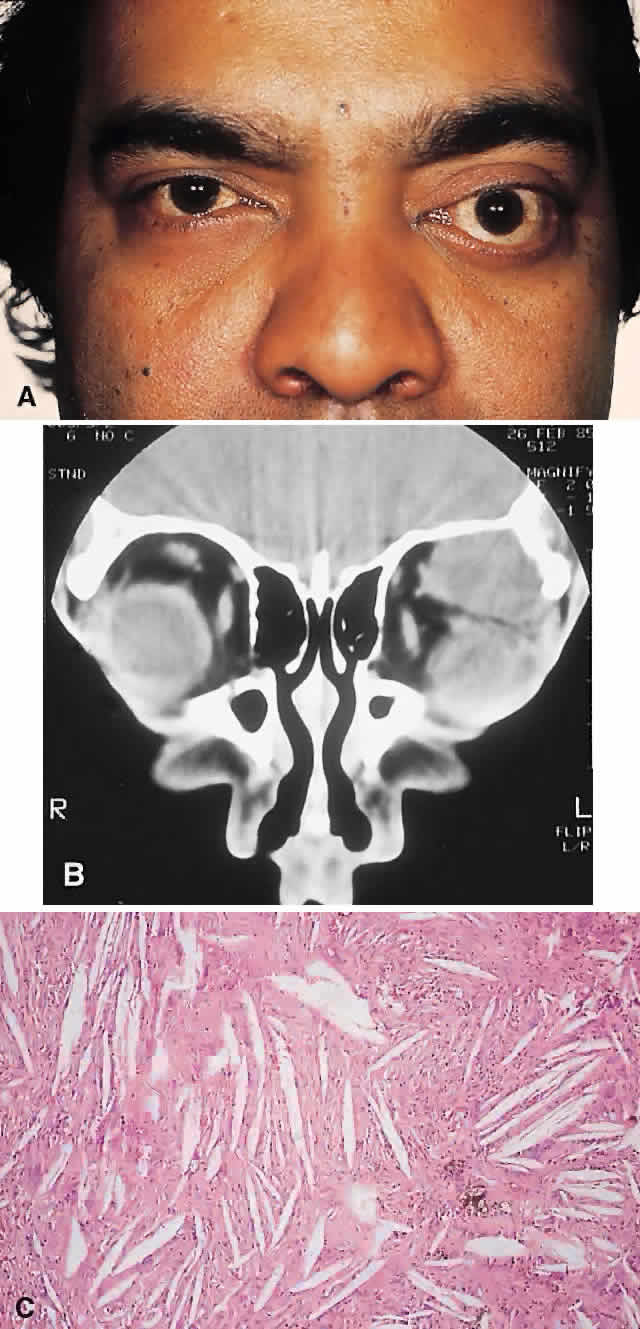

Chondroma

These benign cartilaginous tumors usually occur as asymptomatic lesions in the sinuses and nasal cavity. They rarely occur in the orbit, where they present as slow-growing, painless, firm lumps, often near the orbital rim or the trochlea.64,65 They have on occasion also been described in the soft tissues of the orbit.66 Radiologically, they are seen as well-circumscribed, dense masses that histologically consist of lobulated mature hyaline cartilage. Mature chondrocytes are seen in the cartilage, along with a variable fibrous or myxoid stroma. Surgical excision is always curative.64,67

A variety of other benign cartilaginous tumors, including osteochondromas, enchondromas (Fig. 4), and fibrochondromas, have also rarely been described in the orbit, although the histologic documentation is not always convincing.68

Fig. 4. This 25-year-old woman had a 6-month history of a hard lump, which was readily palpable at the superomedial right orbital rim. A and B. CT showed a 1-cm bony mass that was more radiolucent centrally on bone window setting. C. The histopathology consisted of globules of mature cartilage encased in lamellar bone, leading to a diagnosis of enchondroma (hematoxylin-eosin, × 20).